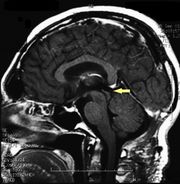

| 17:29, 26 February 2023 | Pienal cavernoma post surgery 2.jpeg (file) |  |

124 KB | 1 | |